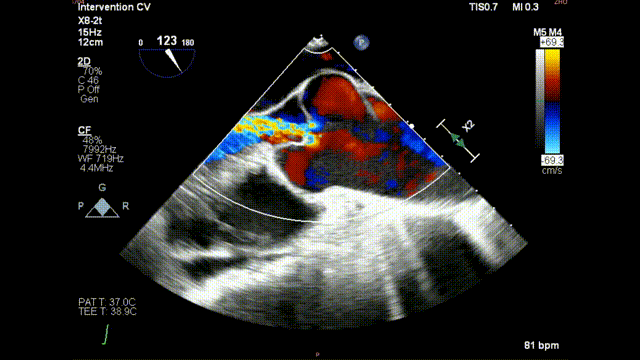

术后食道超声示:

术后食道超声-短轴color

术后食道超声-长轴color

复查造影示人工瓣膜位置,功能,形态良好,左右冠状动脉灌注良好,未见明显反流及瓣周漏;